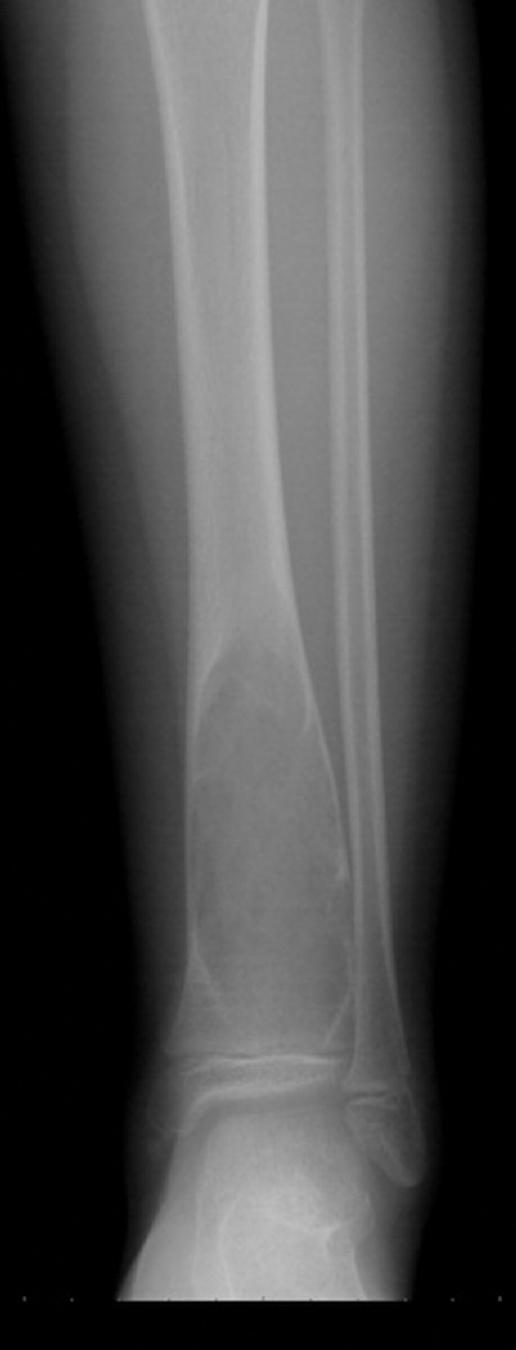

This study consists of patients diagnosed with ABC, who applied to the orthopedics and traumatology clinic of Dicle University Faculty of Medicine. Our study consists of 20 patients diagnosed with ABC (Group 1) (Fig. 1) and 30 healthy patients (Group 2). Age, gender, cyst sizes, and visfatin values of all patients were recorded and evaluated.